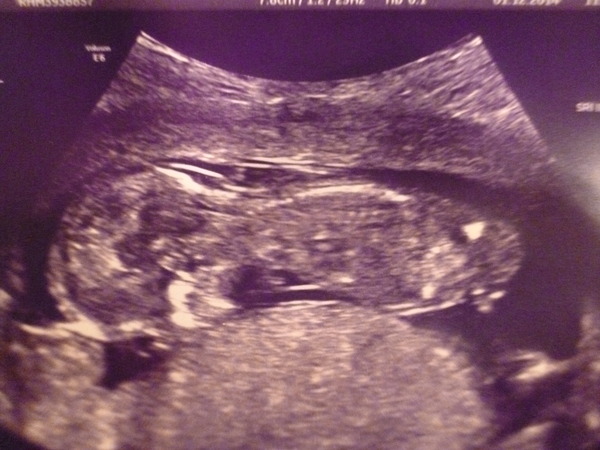

Struggling to keep up with all the chat!

Here's my naughty little monkey, wouldn't get in the perfect position for measurements so they took the nearest one, which has brought my EDD forward to 5th June. Am now 13+3, altho cannot really be more than 13w. Apparently I ovulated from both ovaries so we are (un)lucky that it's just the one! Anterior placenta which may cause me problems for a vbac but will worry about that later. 20w scan booked for 16th Jan.

Unbeknownst to me a friend was also having her 12w scan today (same hosp), she has a EDD of 6th June but at 13+3 as well.

Ememsmum - great scan news and at least you can tell its a baby even if it wouldn't show the camera the right angle.